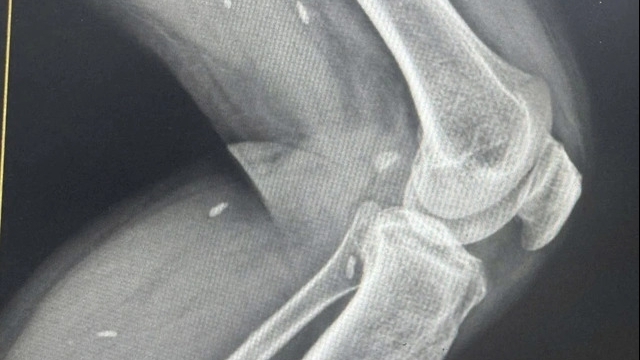

Phòng Khám Đa khoa Hồng Cường rất chú trọng đến trang thiết bị máy móc y tế; Được trang bị đầy đủ và kiểm duyệt chặt chẽ trước khi đưa vào sử dụng, bảo dưỡng định kì đảm bảo vận hành tốt và suôn sẻ, tránh sai sót.

Kỹ thuật khám và điều trị bệnh tại Phòng khám Đa khoa Hồng Cường vô cùng hiện đại, tiên tiến. Thông qua kiểm tra thăm khám kỹ lưỡng, tùy vào từng bệnh lý, mức độ bệnh, tình trạng sức khỏe hiện tại của bệnh nhân mà bác sĩ sẽ có những chỉ định phù hợp nhất, có thể là điều trị nội khoa (dùng thuốc) hoặc can thiệp ngoại khoa điều trị nhằm đem đến hiệu quả tối ưu.